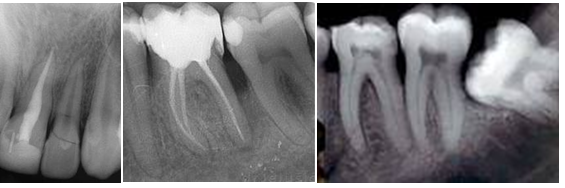

Endodontija (zdravljenje zobnih korenin)

Zdravljenju zobnih korenin namenjamo posebno pozornost. Pri obravnavi odstranimo bakterijsko okužbo iz koreninskih kanalov in zapolnimo kanale pri čemer dosegamo visoke kriterije za uspešno zdravljenje.

Za ročno in strojno širjenje koreninskih kanalov uporabljamo moderne aparate, inštrumente in materiale.